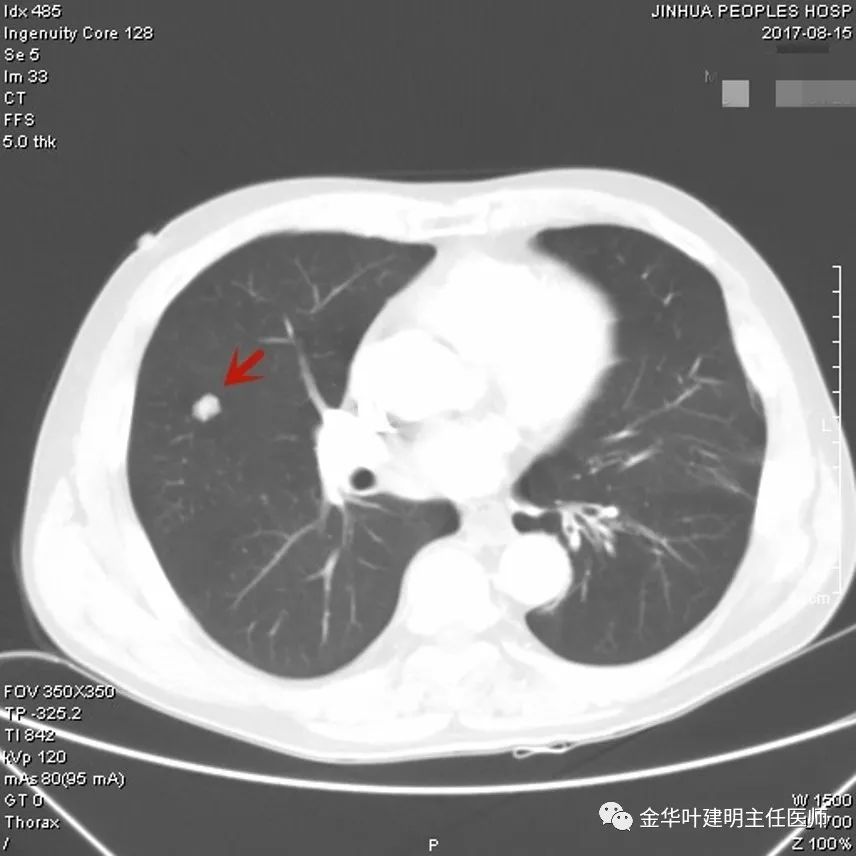

上图示硬化性血管瘤:此结节考虑良性可能性大,但要定具体性质仍是困难的,其密度均匀,边缘非常光滑,没有卫星病灶,没有渗出改变,收缩力不明显(邻近胸膜无牵拉)。